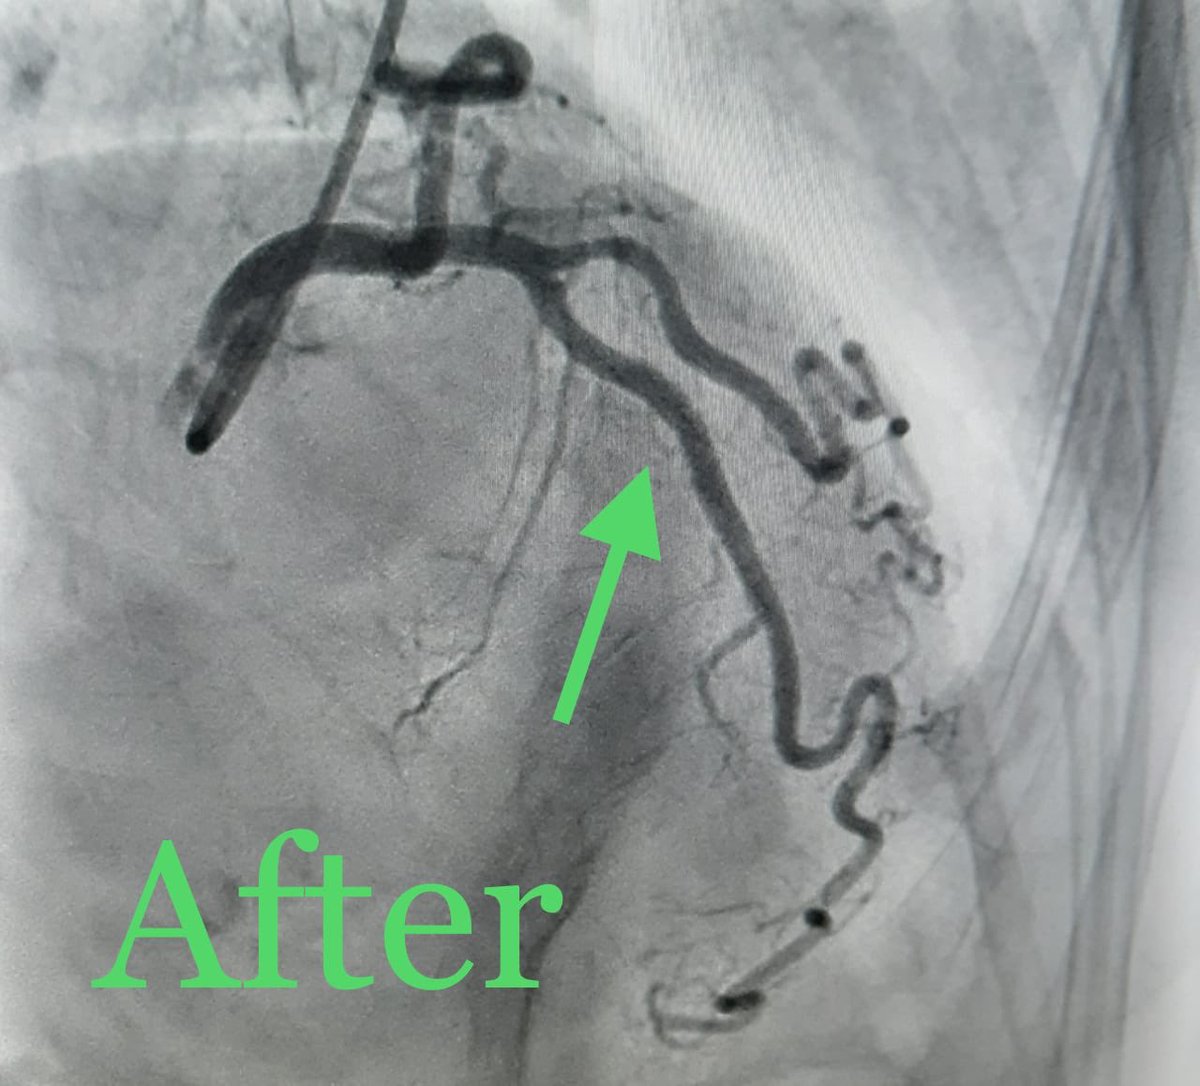

تعاملنا اليوم مع احدى الحالات من هذه الفئة العمرية العزيزة على قلوبنا، مريضة ثمانينية حضرت للطواري باعراض غير نمطية لتصلب الشرايين، تم تشخيصا و علاجها و لله الحمد